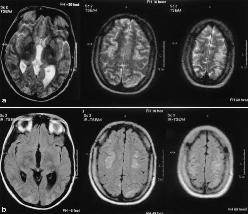

血卟啉病性周圍神經病急性間歇性卟啉病的周圍神經病表現與吉蘭-巴雷綜合徵相似,容易誤診前者有腹痛腎區腰痛、精神異常明顯的心律失常以及腦脊液蛋白正常或僅輕微升高可資鑑別。鉛中毒和卟啉病均可有肢體癱瘓、腹痛心律失常高血壓和腦病且鉛中毒也可有卟啉代謝障礙,二者易混淆。但鉛中毒時尿中糞卟啉和ALA的排除量明顯增加而尿中尿卟啉和卟吩膽紅素原僅有輕度升高此點與卟啉病不同鉛中毒時血鉛水平升高可資二者進行鑑別。此外急性間歇性卟啉病的腹痛易被誤診為急腹症而行手術探查;精神症狀易誤診為精神分裂症或腦炎;皮膚改變易誤診為凍瘡,臨床應注意鑑別。